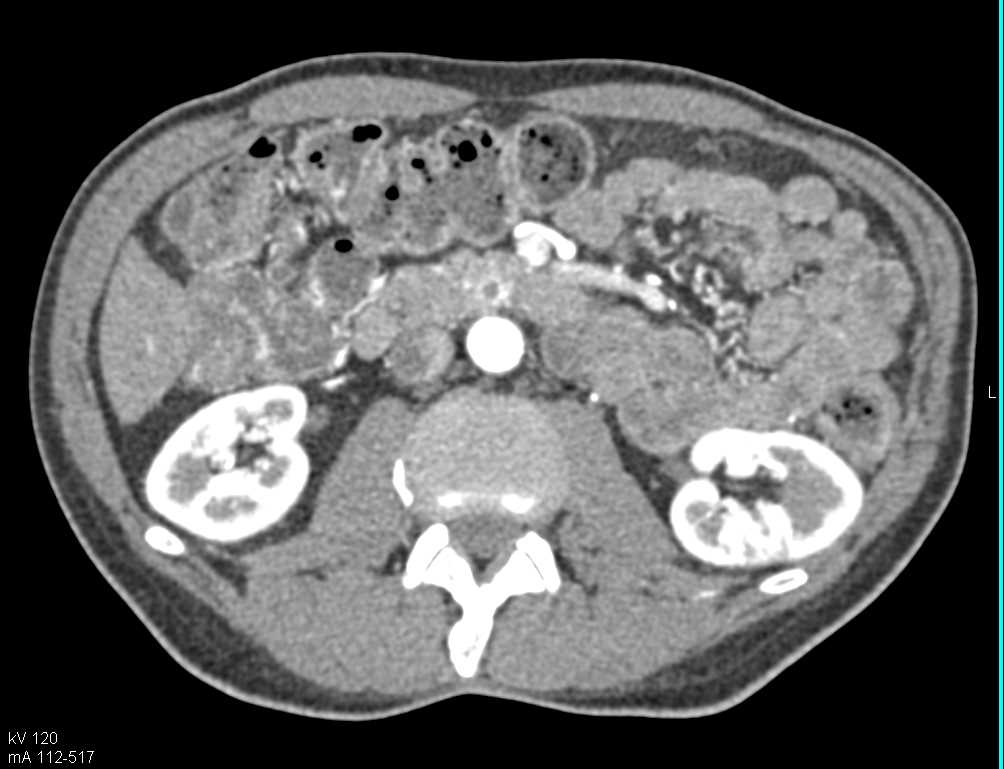

Multiple Intraductal Papillary Mucinous Neoplasms (IPMNs)